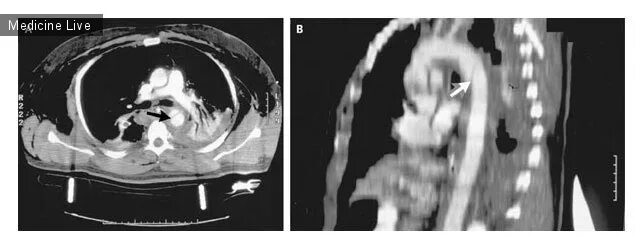

От чего бывает разрыв аорты